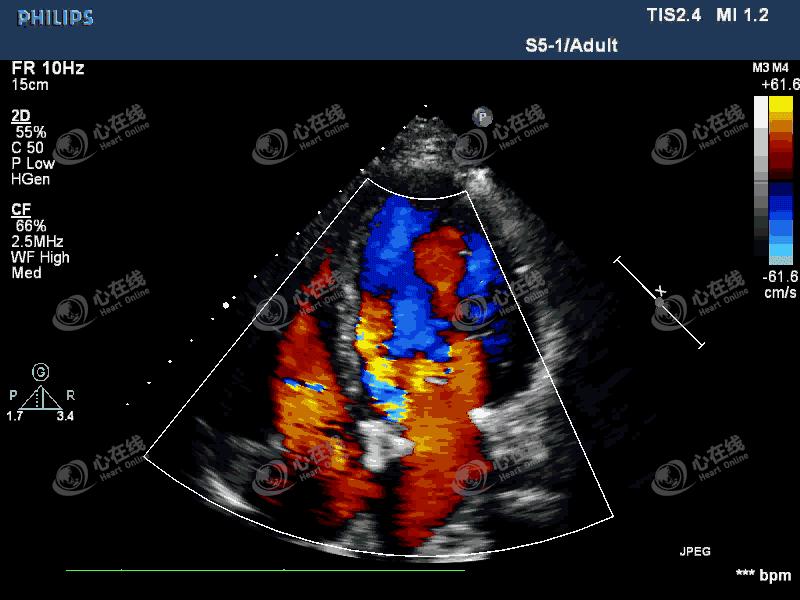

图3 四腔心切面:彩色多普勒显示中量偏心性反流信号,起自主动脉瓣机械瓣环外侧。